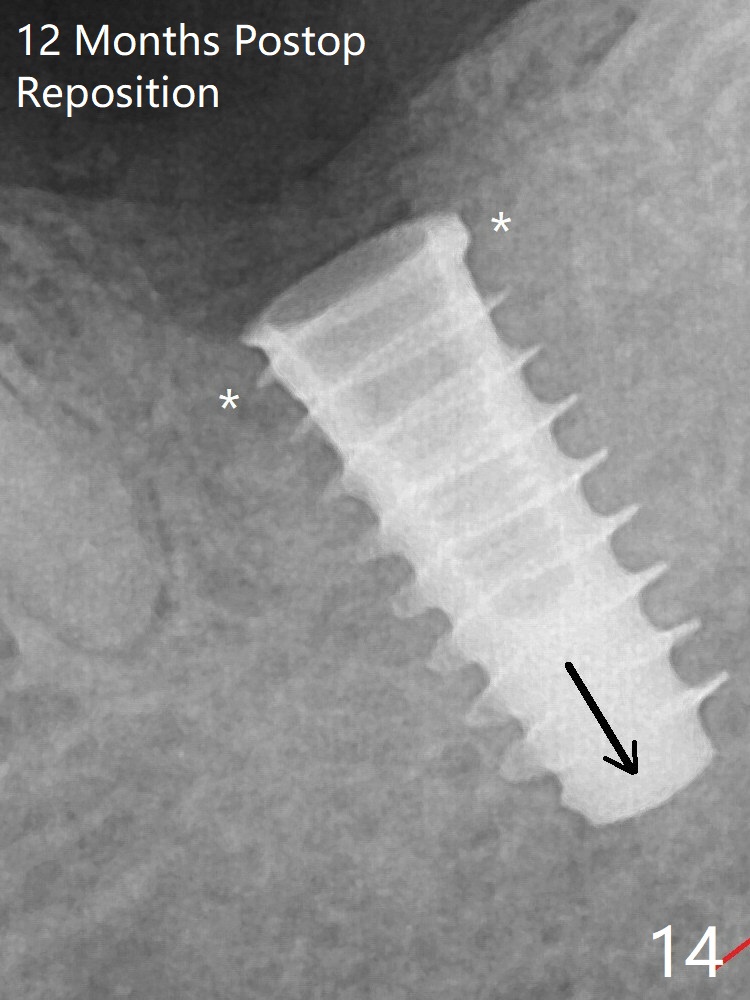

The implant is removed, cleaned with Titanium brushes and H2O2 in vitro and repositioned 12 months postop (Fig.14: arrow (gaps: post granulation tissue removal)). The gaps are regrafted with sticky bone and covered with PRF membrane and Cytoplast.取出植体,钛刷清洗,即刻植入,种深些(图十四:箭头),冠部螺纹两旁有间隙(*);放置愈合帽,最后表浅放置粘性骨粉(图十五:*)。覆盖不可吸收膜,